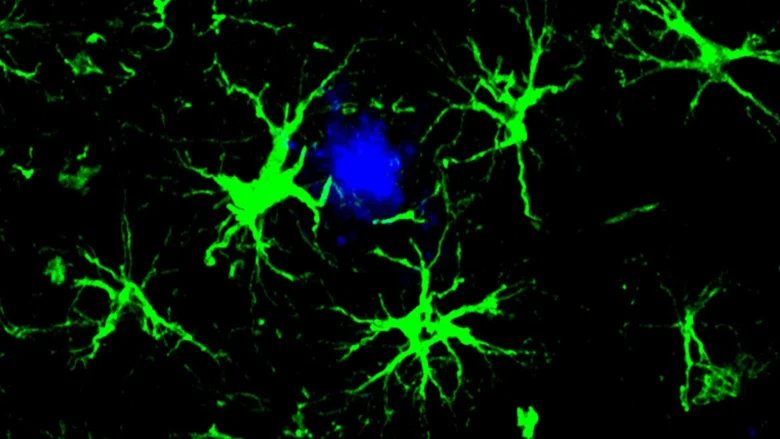

The new strategy is inspired by CAR-T cell therapies used in cancer treatment. In those therapies, immune T cells are genetically engineered to identify and attack cancer cells. In this Alzheimer’s approach, scientists modified a different type of cell. They equipped astrocytes, a common type of brain cell, with a CAR homing device that allows the cells to latch onto specific targets and destroy them.

These engineered CAR-astrocytes act like powerful cleaning cells in the brain. Their design allows them to locate and remove harmful proteins that contribute to cognitive decline.

Chen redesigned astrocytes to become specialized amyloid clearing cells. He introduced a gene that produces a chimeric antigen receptor (CAR) into astrocytes using a harmless virus injected into mice. Once expressed on the surface of the astrocytes, the CAR allowed the cells to capture and swallow amyloid beta proteins. With this added ability, the astrocytes concentrated on removing amyloid beta plaques in mice that are prone to developing them. Astrocytes normally help maintain order in the brain.